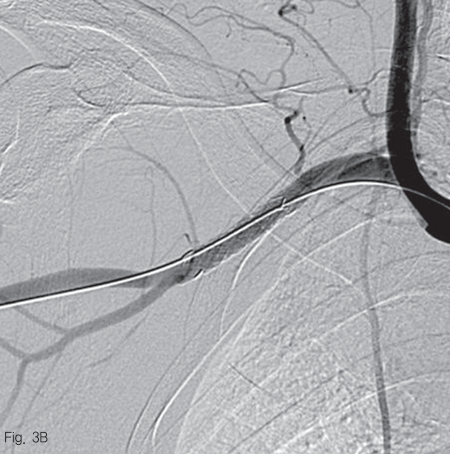

우측 대퇴동맥을 천자하여 5 Fr sheath를 거치 후, 0.035 인치 guidewire (Terumo Corp., Somerset, NJ, USA)를 이용하여 5 Fr Headhunter catheter (Cook Medical, Bloomington, IN, USA)를 팔머리동맥 근위부에 위치시킨 후 동맥 조영술을 시행하였다. 우쇄골하 동맥과 액와 동맥의 경계 부위의 위측에 조영제의 혈관외유출과 이로 인한 가성동맥류 형성을 확인하였다 (Fig. 2). 조영제 유출이 보이는 동맥의 직경은 약 6.2 mm 였으며, 거치된 카테터를 통해 Amplatz super stiff wire (Boston scientific, Natick, MA, USA)로 교체 후, 이 부위를 8 mm 직경의 4 cm 길이 자가팽창 covered 스텐트-그라프트 (vascular stent-graft, TaeWoong Medical, Gimpo, Korea)를 삽입하였다 (Fig 3A). 시술 후 우쇄골하 동맥조영술을 시행하였을 때 조영제 유출은 보이지 않았으며 (Fig. 3B), 우측 흉견봉동맥, 외측흉동맥, 견갑하동맥의 혈류가 잘 관찰되었다.

Fig 3B

The postimplantation angiography shows patent right subclavian atery without active bleeding